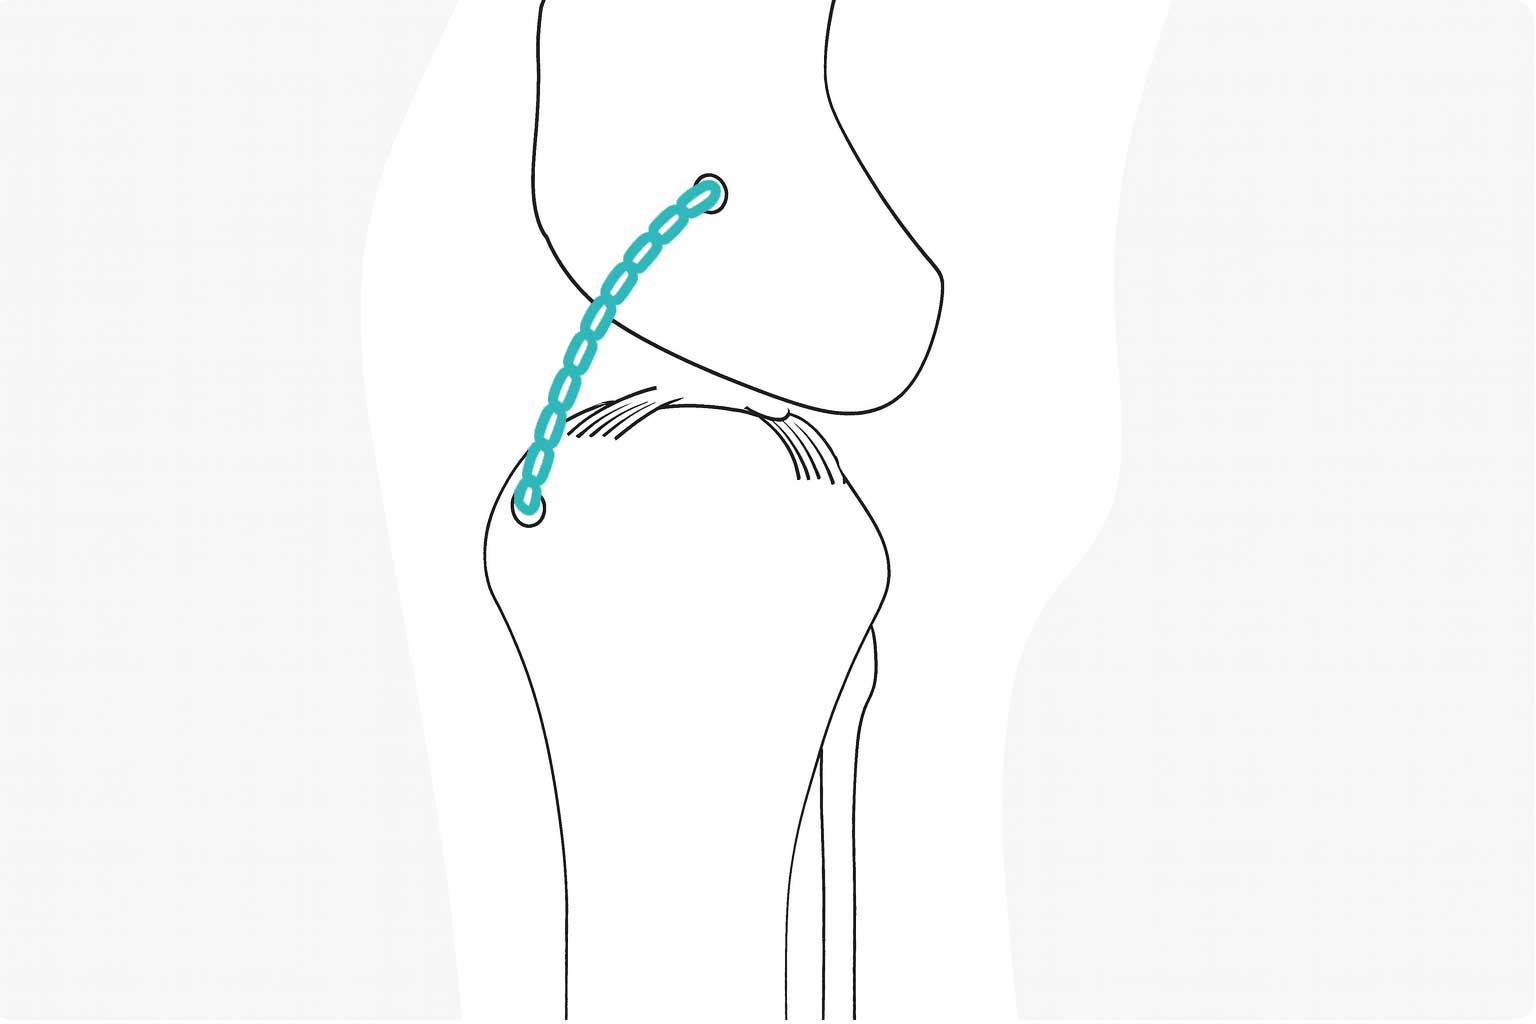

전십자인대(Cranial Cruciate Ligament) 단열은 무릎 속 인대가 부분적으로 또는 완전히 찢어지거나 박리된 상태를 말합니다.

이 인대가 손상되면 무릎 관절에서 정강이뼈가 앞쪽으로 밀려 불안정해지며, 외상이나 슬개골 탈구, 퇴행성 관절염, 비만 등 다양한 원인으로 발생할 수 있습니다. 이러한 손상은 반려동물에게 기력 저하, 산책 거부, 절뚝거림, 통증 호소와 같은 증상으로 나타나며, 조기 진단과 치료가 이루어지지 않으면 만성 관절 질환으로 이어질 수 있습니다.

안정성을 더한 맞춤 수술 케이스 -